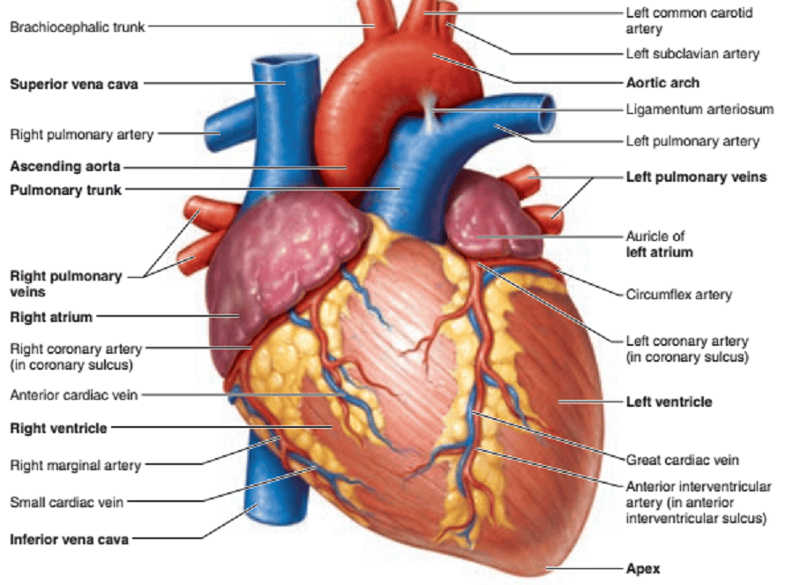

Name the missing parts.

Heart external posterior view